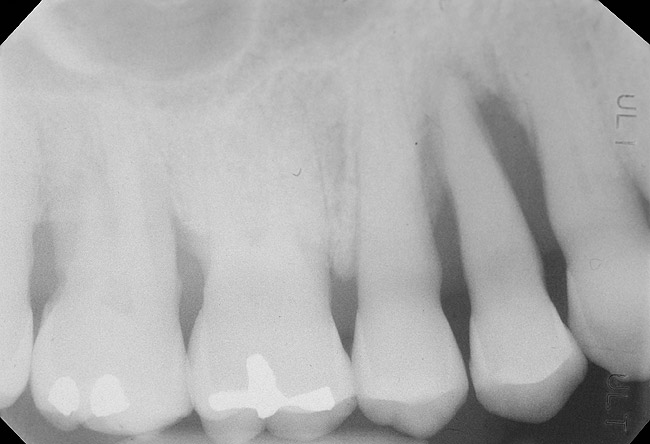

The clinician also must consider the status of the adjacent teeth. Figure 6 shows teeth Nos. 29 and 31 prepared for a fixed bridge. Factors to be considered in this example were the short root of tooth No. 29 with a distal biologic width violation and a short root trunk on tooth No. 31 (which leads to furcation involvement with a small amount of facial or lingual bone loss). This patient also had periodontal disease, which further decreased the long-term prognosis of the fixed bridge option. No prospective studies directly compare the longevity of the two options: a three-unit fixed bridge vs an implant.37 Other factors that complicate comparisons of an implant vs a fixed three-unit bridge are the variability of fixed bridges as well as the variability of the implants (amount of bone, implant length, etc). For example, endodontically treated abutment teeth do not last as long as nonendodontically treated abutment teeth.38 Restorations on teeth with endodontic posts and a minimal length of ferrule do not persist as long as those on teeth without a post and at least a 2-mm ferrule.39

Figure 6   Tooth No. 29 with the temporary build-up close to the osseous crest. Tooth No. 29 has a short post, and tooth No. 31 has a very short root trunk.

Figure 6